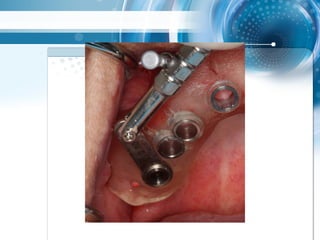

2 mm guide, multiple Extraktionen mit

zahngestütytem drill guide über 3

Zähnen als strategischer Support

2 mm guide,multiple Extraktionen mit zahngestütytem drill guide über 3 Zähnen als strategischer Support

• 71.